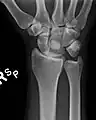

The lunate bone is the most frequently dislocated carpal bone.

Dislocated lunate